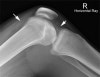

3) Moderate Large

This is evident from the fluid density seen in the supra-patella pouch (left arrow) and in Hoffa's fat pad (right arrow).

A knee effusion indicates an intra-capsular injury (but not necessarily a fracture).